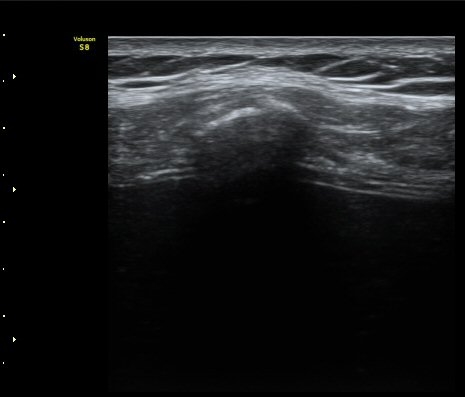

¹Ì¼¼ÇÏ°Ô °¥ºñ»À ÇÇÁú°ñ ¿¬°á¼º ¼Ò½ÇÀÌ °üÂûµÊ(loss of cortical continuity of rib)  »çÁø 1, 2

°¥ºñ»À ¹Ì¼¼°ñÀýÀÌ È®ÀÎ µÊ